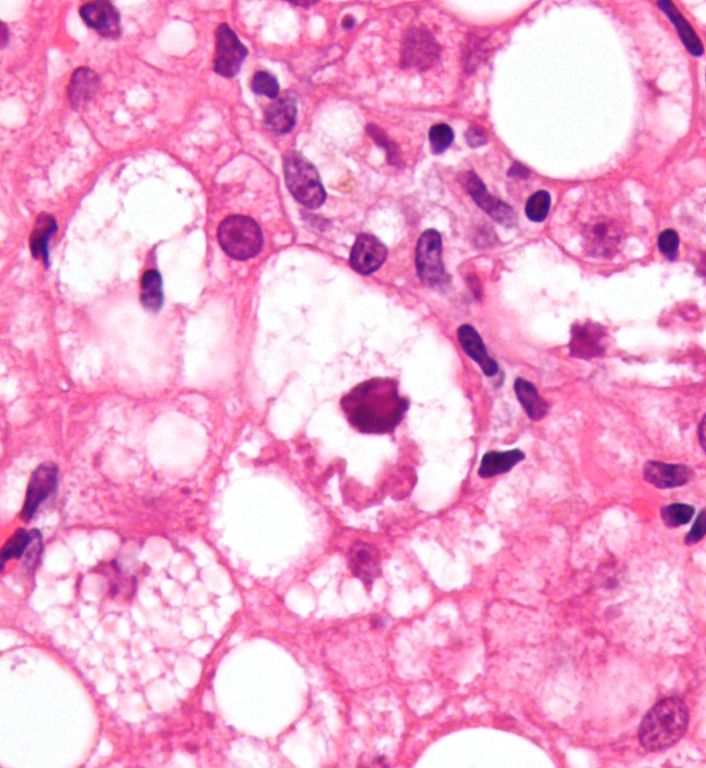

The disease was initially formally known as Primary Biliary Cirrhois (PBC). It has now been changed to Primary Biliary Cholangitis, because it involves a variety of physiological effects—more than just cirrhosis of the liver. Among the general population PBC is rarely found. But as it affects First Nations at a rate of two in every 2,000, the disease develops eight times higher than with non-First Nations people. PBC is even more common in aboriginal communities on the West Coast of B.C., where 48 per cent of Canada’s First Nations people with the disease are located. There is no known cure at this time, though there are treatments for it, and preventative measures, as well.

Nonetheless, the disease isn’t pretty, or fun, once it’s developed. And it causes a variety of other problems, too.

“The bile duct kind of disappears and it also causes jaundice. In the First Nations population there seems to be more autoimmune liver disease like this, and like autoimmune hepatitis, the cousin of PBC,” he said.